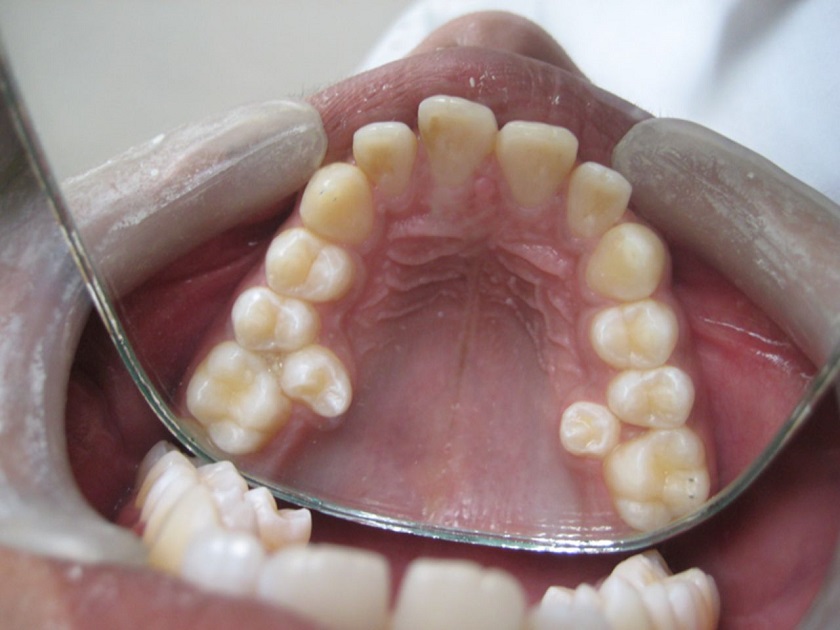

- Răng mọc thừa phát sinh nhiều bệnh lý về răng miệng khi răng tạo thế răng ba chân (gồm 2 răng hàm bình thường và 1 răng thừa) hình thành các rãnh khiến cho thức ăn mắc vào, bàn chải không thể làm sạch hết được mảng bám. Do đó tạo thành môi trường thuận lợi cho vi khuẩn phát triển, lúc này cần phải nhổ răng thừa để giúp cho hàm răng chắc khỏe và thẩm mỹ hơn.

Răng mọc thừa tạo thế răng ba chân